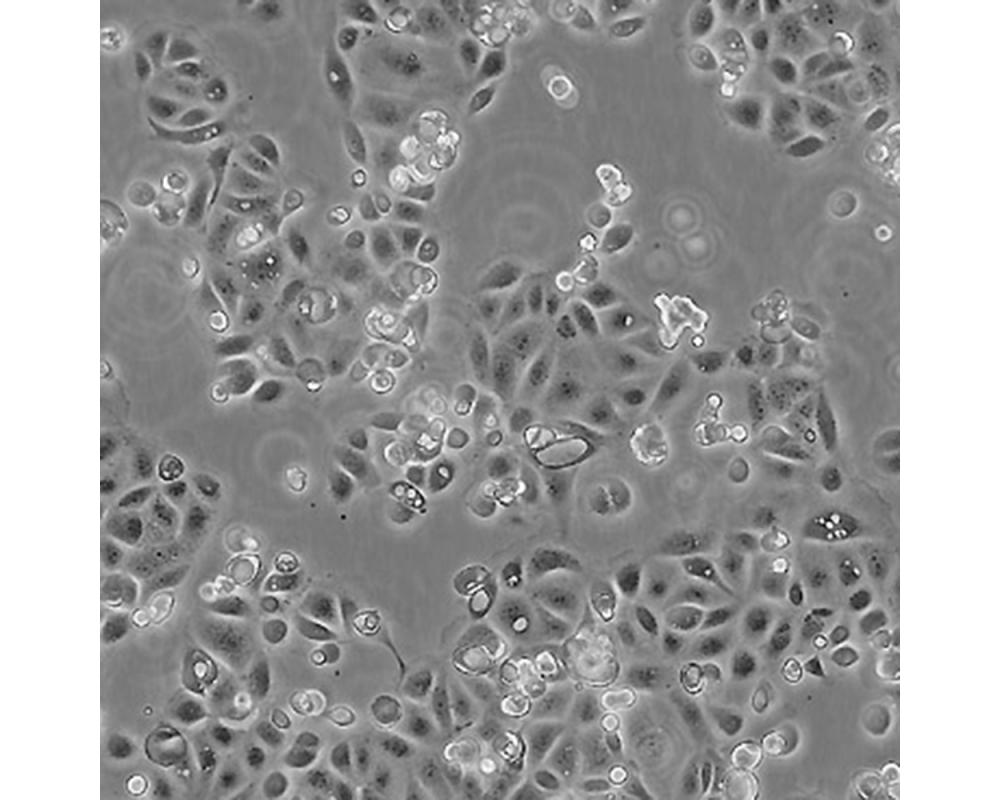

SW1990

中文名稱 人胰腺癌細胞

組織來源 胰腺癌;男性

生長特性 貼壁